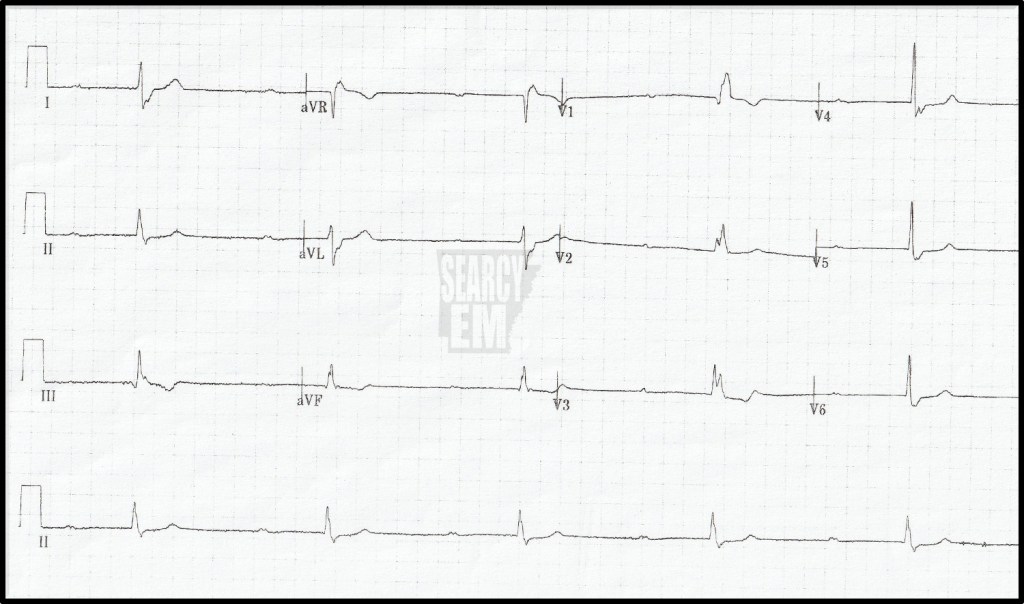

There certainly are lots of nonconducted P waves. However, there is not true “AV dissociation” as the escape rhythm is not regular. That probably means that a P wave is getting conducted occasionally, which would actually indicate a high-grade second degree block. It’s tough to say that any of the QRS complexes are related to a preceding P wave, though. Luckily the distinction is largely academic since we treat high grade second degree blocks the same way we treat third degree blocks.

The escape rhythm is narrow complex and at first glance it does seem that the QRS complexes seem to fall after P waves with a similar PR interval. Those things would indicate a second degree block. However, if you notice the PR interval before the first two QRS complexes, they are too short to be conducted. The last two QRS complexes, on the other hand, have PR intervals that could have been conducted, so those ‘could have’ been sinus beats, which would make this a high grade second degree block. However, the RR intervals are the same across the ECG and are unrelated to the PP intervals. That tells us there is AV dissociation, which means it is a third degree block with an escape rhythm originating from within the conducting system, because the QRS complex is narrow.